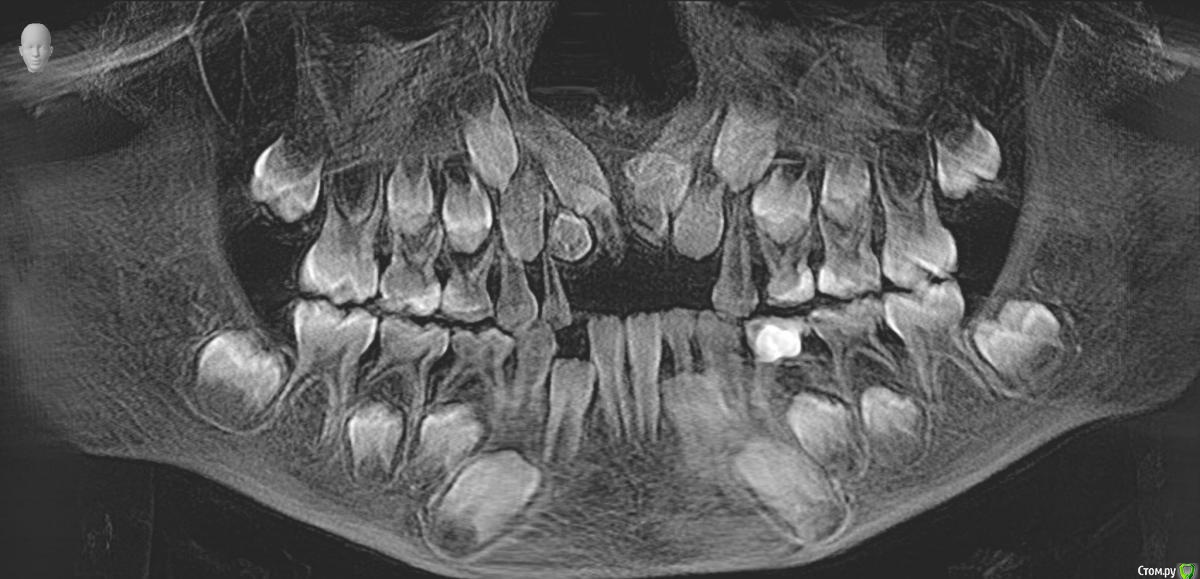

Ребенок 6 лет.

Буду благодарна за Ваше видение картины сверкомплектных и возможные планы варианты лечения.

По теме интересует какие лишние зубы можно дождаться и удалить после прорезывания, какие требуют оперативного вмешательства, какие сроки, тот что на месте 11 не вниз корнем?

Были в 4 клиниках, случай не типичный, варианты лечения разные. От ничего не делать ждать, до резать удалять. Начинали с 2 сверхкомплектов, потом нашли еще два.